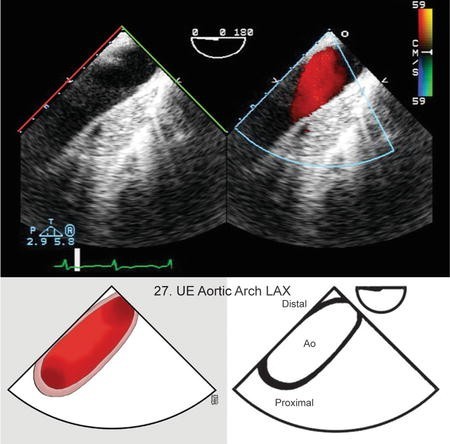

How would you obtain the Upper Esophageal Aortic Arch LAX View?

Insert the probe to the ME, sector depth 4-6cm, angle 0°

Find ME Descending Aorta SAX (0°) view

Withdraw probe until aorta changes into oval shape

Turn probe slightly to the right